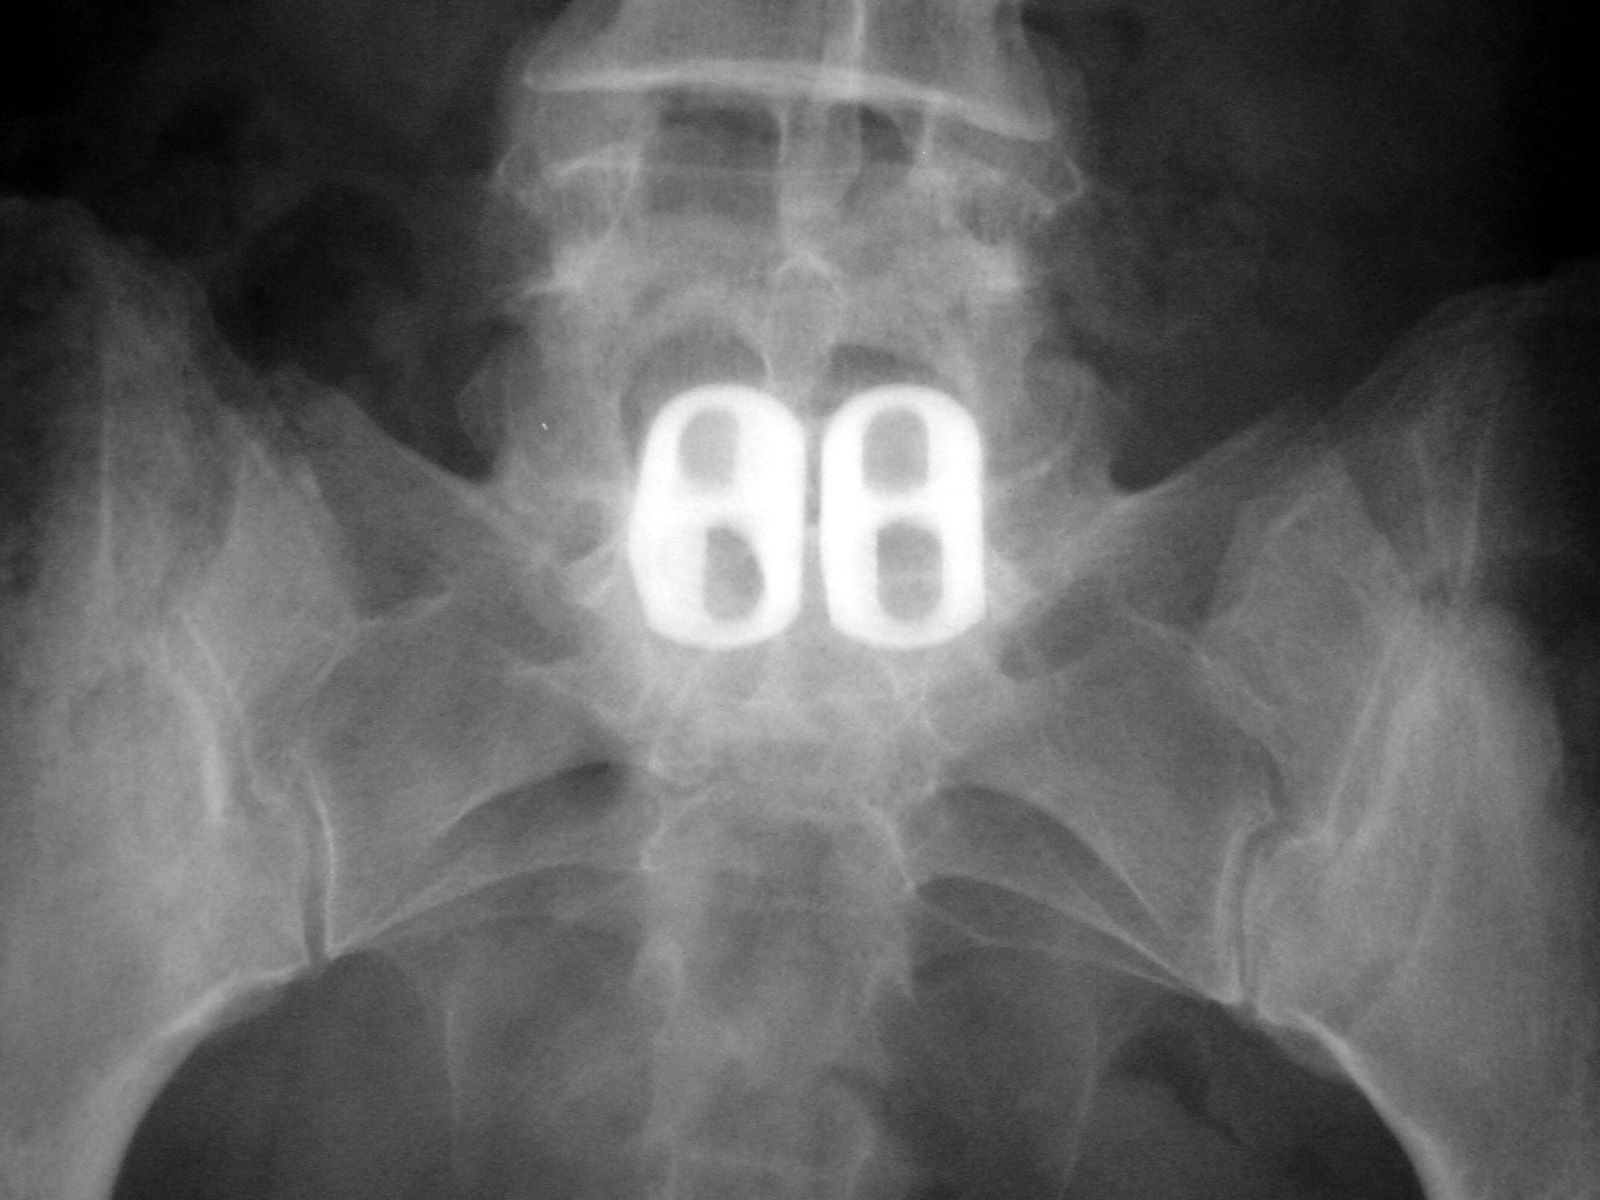

| Sacral stimulator AP and lateral views |

Sacral stimulator |

Hernia mesh is also visible over the lower abdomen and pelvis |